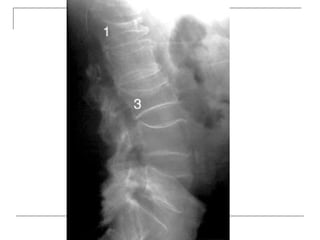

 Lateral

-fracture/wedging

-kyphosis

-spondylolisthesis

 Oblique

-spondylolysis (SCOTTIE DOG)

Plain x-rays